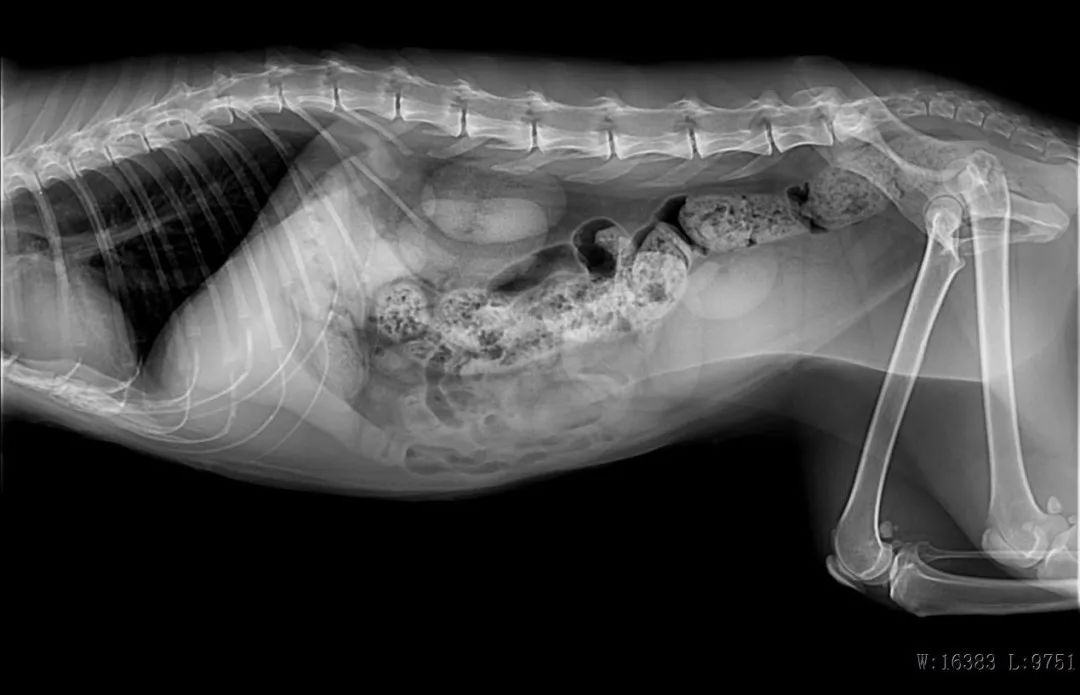

DR检查

B超检查

猫糖尿病、子宫蓄脓感染